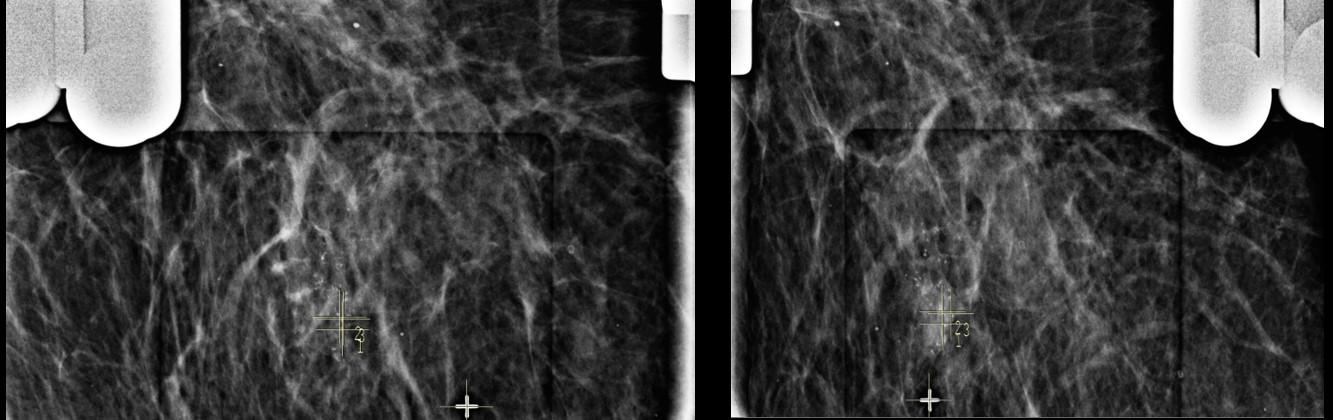

Paciente assintomática de 48 anos, realizou mamografia de rastreio (imagem 1 e 2) que evidenciou um pequeno grupamento de microcalcificações com morfologia pleomórfica e distribuição segmentar, localizado na UQM (união dos quadrantes mediais) da mama direita, não disponibilizou exames anteriores e retornou ao mastologista que solicitou core-biópsia por estereotataxia.

Realizado a análise do menor trajeto para acessar a área referida, a paciente foi posicionada em oblíqua, através da entrada de raios X em médio-lateral com angulação de 50°. As marcações dos alvos foram feitas em duas abordagens distintas (imagens 3 e 6), com objetivo de atingir a maior quantidade de microcalcificações. O procedimento foi realizado sem intercorrências e os fragmentos obtidos foram submetidos a um estudo radiológico demonstrando espécimens adequados com a presença de microcalcificações na amostra (imagens 5 e 7). O resultado anátomo-patológico obtido foi de carcinoma ductal in situ.